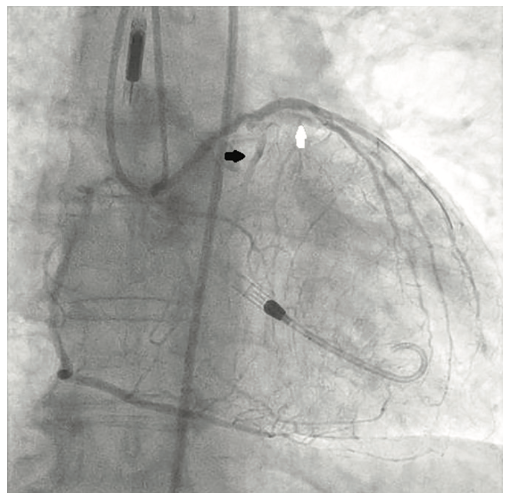

Following the Perclose placement, we upsized to a 14 Fr x 13 cm Cook Medical sheath (Figures 7-8), and through that, advanced a JR catheter into the ventricle and switched out for the Impella 2.5 device (Figure 9). A JR4 and eventually, an Amplatz right (AR) mod, was used from the right ulnar to engage the RCA, and an Extra Backup (EBU) 3.5, 7 Fr (Medtronic) was used from the groin. Dual angiography was performed (Figure 10). Once the activated clotting time (ACT) was >300 seconds, the ramus was wired with a Marvel wire (Boston Scientific). We attempted to cross the LAD CTO using a Corsair (Asahi Intecc) and a Pilot 200 (Abbott Vascular). The Pilot 200 crossed, but it appeared to be in the diagonal and could not be redirected down the LAD. A Gaia second (Asahi Intecc) was able to cross into the LAD (Figure 11), and at that point, was switched out via the Corsair for a workhorse wire, a Runthrough (Terumo). An 0.9 laser (Spectranetics) was used perform laser atherectomy for a minute and a half on the LAD (Figure 12), but we could not get the catheter across. However, this allowed us to advance a balloon across the lesion and we predilated with a 1.5 mm x 20 mm Mini Trek (Abbott Vascular) and then a 2.0 mm x 20 mm balloon. The same 2.0 mm x 20 mm balloon was used in the ramus. A 2.5 mm x 15 mm AngioSculpt (Philips) was used to predilate the LAD, but on its return, the AngioSculpt became stuck and would not come back. We got it partially into the guide and then the shaft broke. We had part of the catheter in the guide and part of it in the coronary (the left main). We initiated a series of procedures to remove the AngioSculpt, first attempting use of a GuideLiner (Vascular Solutions) to envelope the balloon, but this was unsuccessful (Figure 13). The GuideLiner kept pushing the device further out. We tried trapping it; that was also unsuccessful. We were able to get a Mini Trek balloon distal, thinking it could be inflated and pulled back; that did not work. We then put the 4 wires down, wrapped the wires around and pulled back, getting it partially in the guide, but we could not get it all the way in. We got a Mini Trek down, used the GuideLiner to put a 2.0 down, and attempted an anchor technique that did not work, but this time, when we pulled the Mini Trek 2.0 back, it dislodged the balloon. The AngioSculpt was able to come in the guide and was removed without losing wire position. We rewired the ramus, performed dilation of the LAD and ramus with a 2.5 mm noncompliant balloon, and performed intravascular ultrasound (IVUS). The LAD was about 2.75 mm2 distally and the ramus was 3.0 mm2, with the left main being approximately 3.75 mm2. A double kissing (DK) crush technique was used with a 2.75 mm x 38 mm Synergy stent (Boston Scientific) to the LAD and 3.0 mm x 24 mm Synergy to the ramus; then we used proximal optimization technique (POT) with a 3.75 mm NC balloon (Medtronic) and a final kiss with 3.0 mm x 20 mm NC balloons (Figures 14-17). IVUS was used to confirm that the stents were well apposed. The Impella device was weaned and removed, keeping the sheath in. From the groin sheath, a balloon was advanced into the left subclavian and we did a dry close. We inflated an 8.0 mm x 40 mm balloon at 3 atmospheres (nominal is 6 atmospheres) (Figure 18). Once the pressure tracing from the axillary sheath side arm dropped, we were able to remove the sheath and then completed the Perclose. There was some slight track ooze (Figure 19). Therefore, we performed two 5-minute inflations with the 8.0 mm x 40 mm balloon at 3 atmospheres (nominal is 6 atmospheres), and there was complete resolution of the track ooze. No extravasation was noted (Figures 20-21). The ulnar sheath was sutured in, we made sure there were no issues overnight, and the patient was discharged the following morning.

An axillary access site requires meticulous steps to guarantee safe implantation and explantation of the sheath. If time permits, two Perclose sutures are deployed at 10 o’clock and 2 o’clock before insertion of the large-bore sheath. In emergent cases, when there is no time for Perclose insertion, our strategy is the following: the sheath is removed and an 8-10 mm diameter balloon (based on the vessel size) from an alternative access (ipsilateral radial artery or femoral artery) is delivered to the arteriotomy site. Then the sheath is removed and the balloon is inflated at the arteriotomy site at 3-4 atmospheres (depending on the size of the vessel) until any oozing stops. The balloon stays inflated in place for 15-30 minutes over the arteriotomy site to achieve hemostasis. If the final angiogram showed extravasation at the access site, another prolonged balloon inflation is used. If balloon and manual compression fails, then a covered stent can be used as final bail-out strategy. In cases of a small axillary artery that is large enough to accommodate the sheath but does not allow distal flow beyond the access point, certain interventions can be done to assure sufficient perfusion to maintain limb viability. Using ultrasound guidance, a micropuncture needle is used to get access to the ipsilateral brachial artery. Distal to the Impella sheath, a 5 Fr sheath is advanced into the brachial artery. The side arm of the Impella and 5 Fr sheath are then connected using a male-to-male connector, creating a continuous flow from the Impella sheath to the side arm of the 5 Fr sheath located in the brachial artery. Flow via this bypass can also then be confirmed distally via Doppler or using standard angiography.